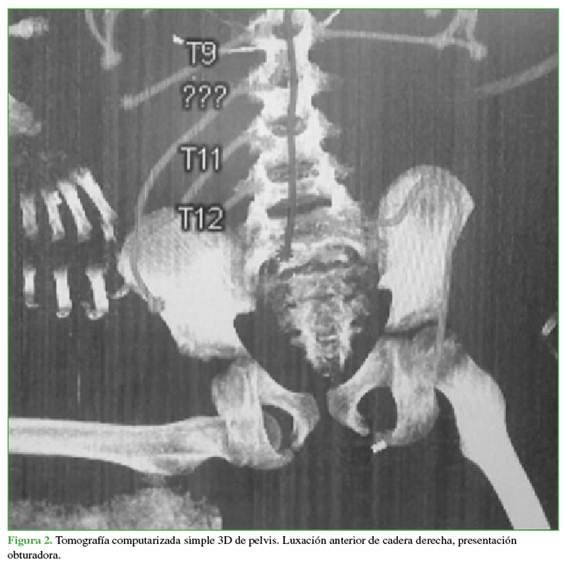

En las radiografías de control a los 3 (Figura 4) y 6 meses (Figura 5), no se visualizaron hallazgos de NAV y también se descartaron otras complicaciones osteomusculares asociadas a la luxación traumática.

Entre las complicaciones descritas se destacan las siguientes: coxa magna, parálisis del nervio ciático, parestesias y NAV de la cabeza femoral.10 En pacientes menores de 18 años, su incidencia tras una luxación aislada oscila entre el 3% y el 15%,17 y es más alta si la reducción fue tardía.18 Por ello, el seguimiento con imágenes es fundamental. Si bien no hay consenso sobre los tiempos ideales; en este caso, se realizaron controles a los 3 y 6 meses, y no se detectó evidencia radiográfica de NAV.

Las radiografías de control no mostraron signos sugestivos de NAV (esclerosis, colapso, quistes, reducción del espacio articular, etc.).22 Estos hallazgos pueden demorar de 2 a 6 meses en hacerse visibles en las radiografías,20 por lo que la temporalidad del seguimiento fue adecuada.

A pesar de la ausencia de hallazgos radiológicos de NAV hasta los 6 meses, es necesario continuar con un protocolo de seguimiento con estudios por imágenes en búsqueda de signos de desarrollo de NAV, que pueden demorar hasta 2 años en manifestarse.25